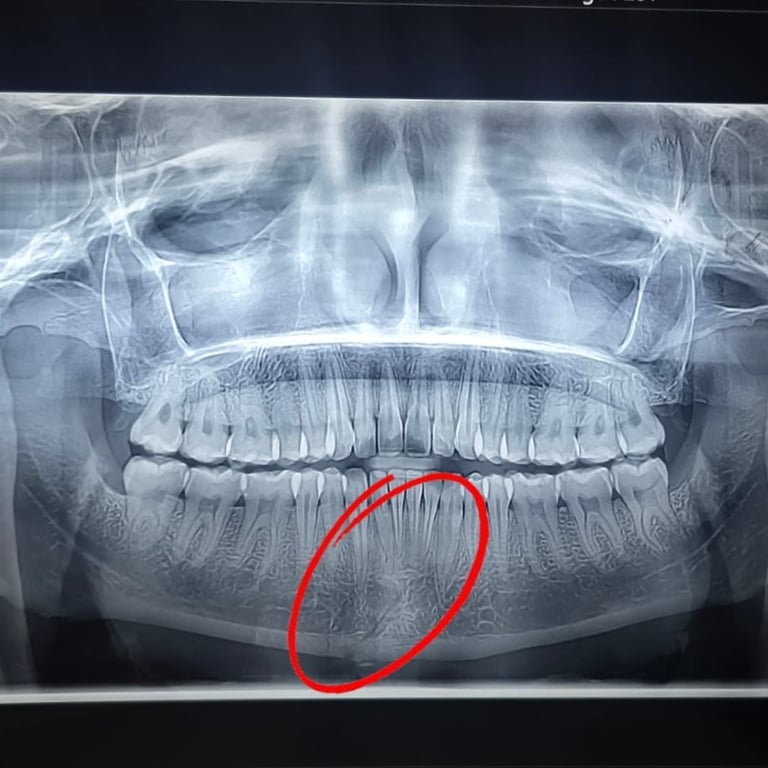

LOWER JAW FRACTURE

treatment includes diagnosis, jaw alignment, and bone fixation. Get expert care for broken jaw pain, swelling, and difficulty in chewing.

See how we treated a parasymphysis mandibular fracture in an 18-year-old male using IMF & plating. Scar-free recovery in just 15 days.